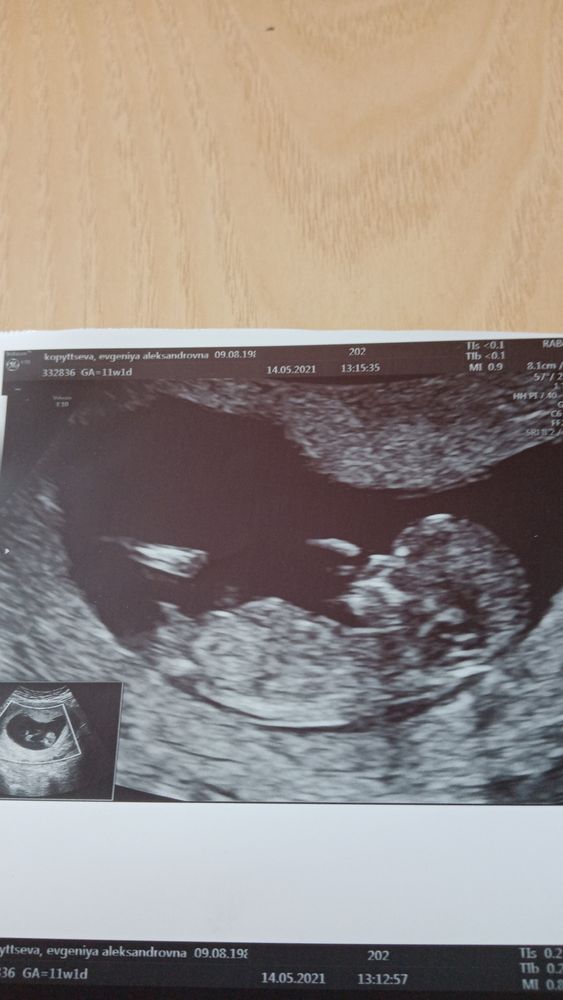

Мальчик скорее всего.Но очень желаю вам девочку!Это может быть и не половой бугорок!

От души желаю вам девочку! 🌺🌺🌺

По фото мне кажется больше на мальчика похоже, посмотрите у меня в дневничке пост про 1 скрининг, там фото есть, мне кажется примерно одинаково - у нас мальчик, я кровь сдавала.